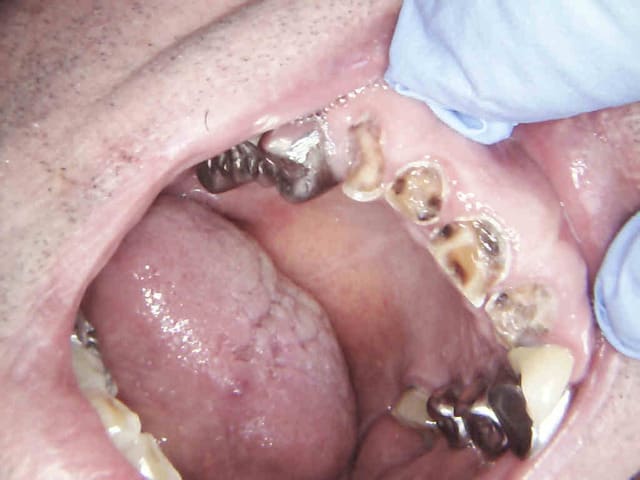

Et 2 autres pour terminer la journée. Ca fait 5 endos molaires aujourd'hui.

Pas trouvé de MV2 sur la 7.